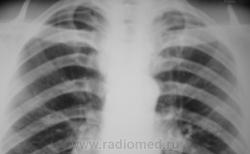

Фактически, эти три случая, часть эксперимента (все не представлено, да и не нужно), который был проведен фтизиатрами и рентгенологами с полным соблюдением стандарта.

Очень часто на пленочной рентгенограмме, и это общеизвестно, мы, в основном, видим «плотненькое» и «обызвествленное». Не можем мы видеть на рентгенограмме «мягкое», а иногда и средней интенсивности, скрытое за костными компонентами грудной клетки. Сравнивая «пленочную рентгенограмму» с цифровой рентгенограммой фиксируется значительная разница теневой картины.

Вот, мы и провели эксперимент, а именно обзорная на пленке, а томограмма – на «цифре».

Какие мнения будут уважаемые коллеги? Не все можно объяснить «цифровым фотошопом» и отсутствием «экранной нерезкости» на цифровых снимках…